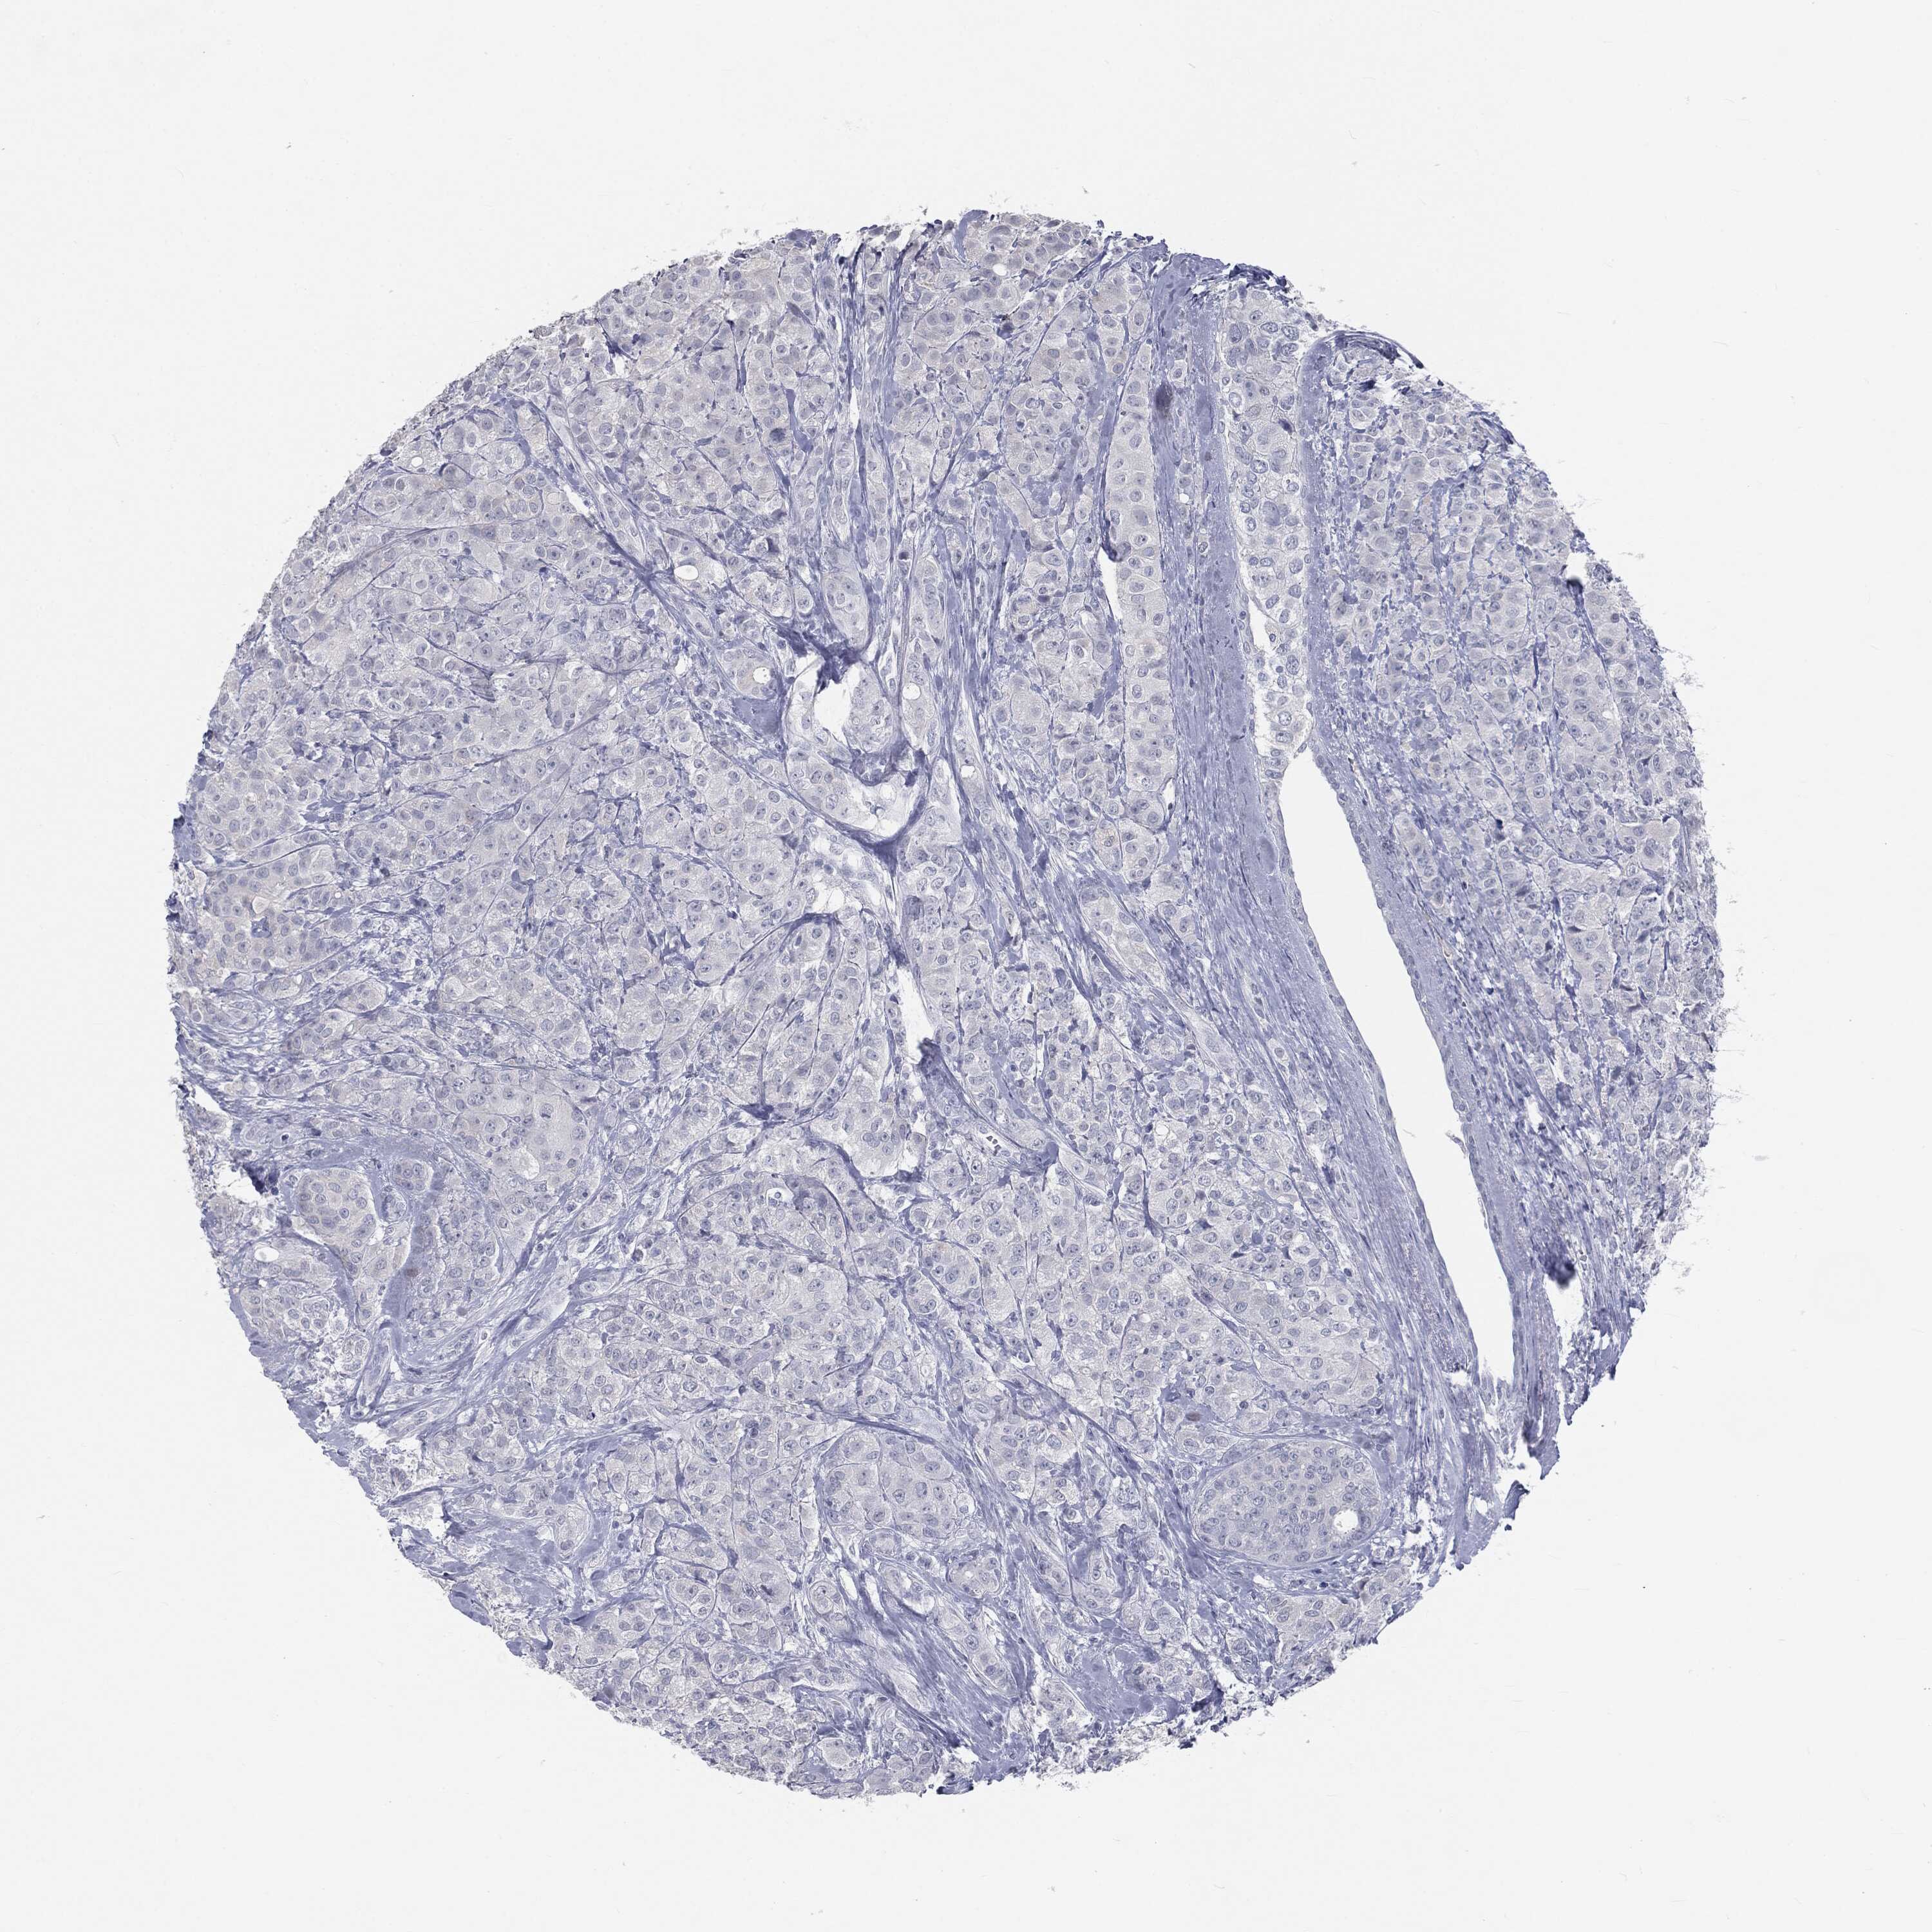

CANCER BREAST CANCER Show tissue menu

BRCA TCGA BRCA VALIDATION PROTEIN EXPRESSION